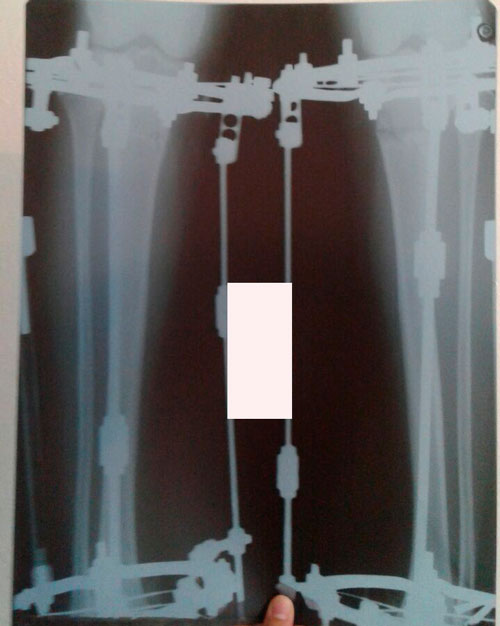

Исходник - 22 года.

Ротация справа под вопросом.

Дата операции 29.03.2016г.